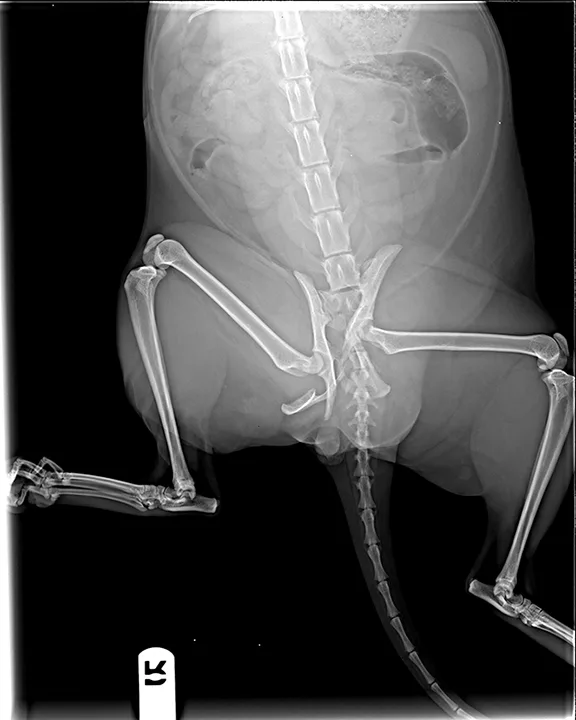

FIGURE 1

Cat with sacroiliac luxation and ischial fractures